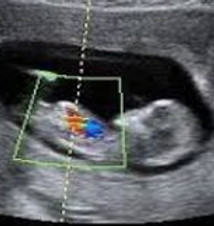

En FEMSALUD contamos con una sección especializada dedicada a brindarte información detallada sobre los diversos tipos de imágenes ginecológicas y obstétricas que realizamos. Nuestro compromiso es ofrecerte estudios precisos y confiables, con tecnología de punta y personal altamente capacitado, para acompañarte en cada etapa de tu salud femenina y reproductiva.